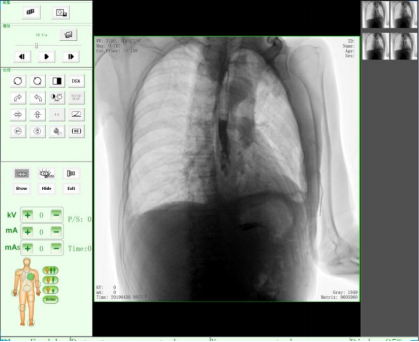

動態(tài)DR17*17英寸非晶硅動態(tài)平板探測器,透視像素達200萬,可實時顯示大幅面高清拍攝視野。適用于全身各部位攝影,包括常規(guī)攝影,如胸片、頸椎、腰椎、腹部、頭顱、四肢等,以及特殊攝影。

三、數(shù)字化透視

適用于全身各部位的透視檢查及輔助治療,如隱匿性肋骨骨折、胸透檢查、骨折復(fù)位、小兒腸套疊空氣灌腸等。同時具備多種幀率透視模式,影像更加流暢、準(zhǔn)確。

五、塵肺檢查片

可進行塵肺檢查應(yīng)用,為塵肺病的即時評估、及時預(yù)防提供巨大價值。同時,可在動態(tài)下觀察塵肺,使診斷更準(zhǔn)確。